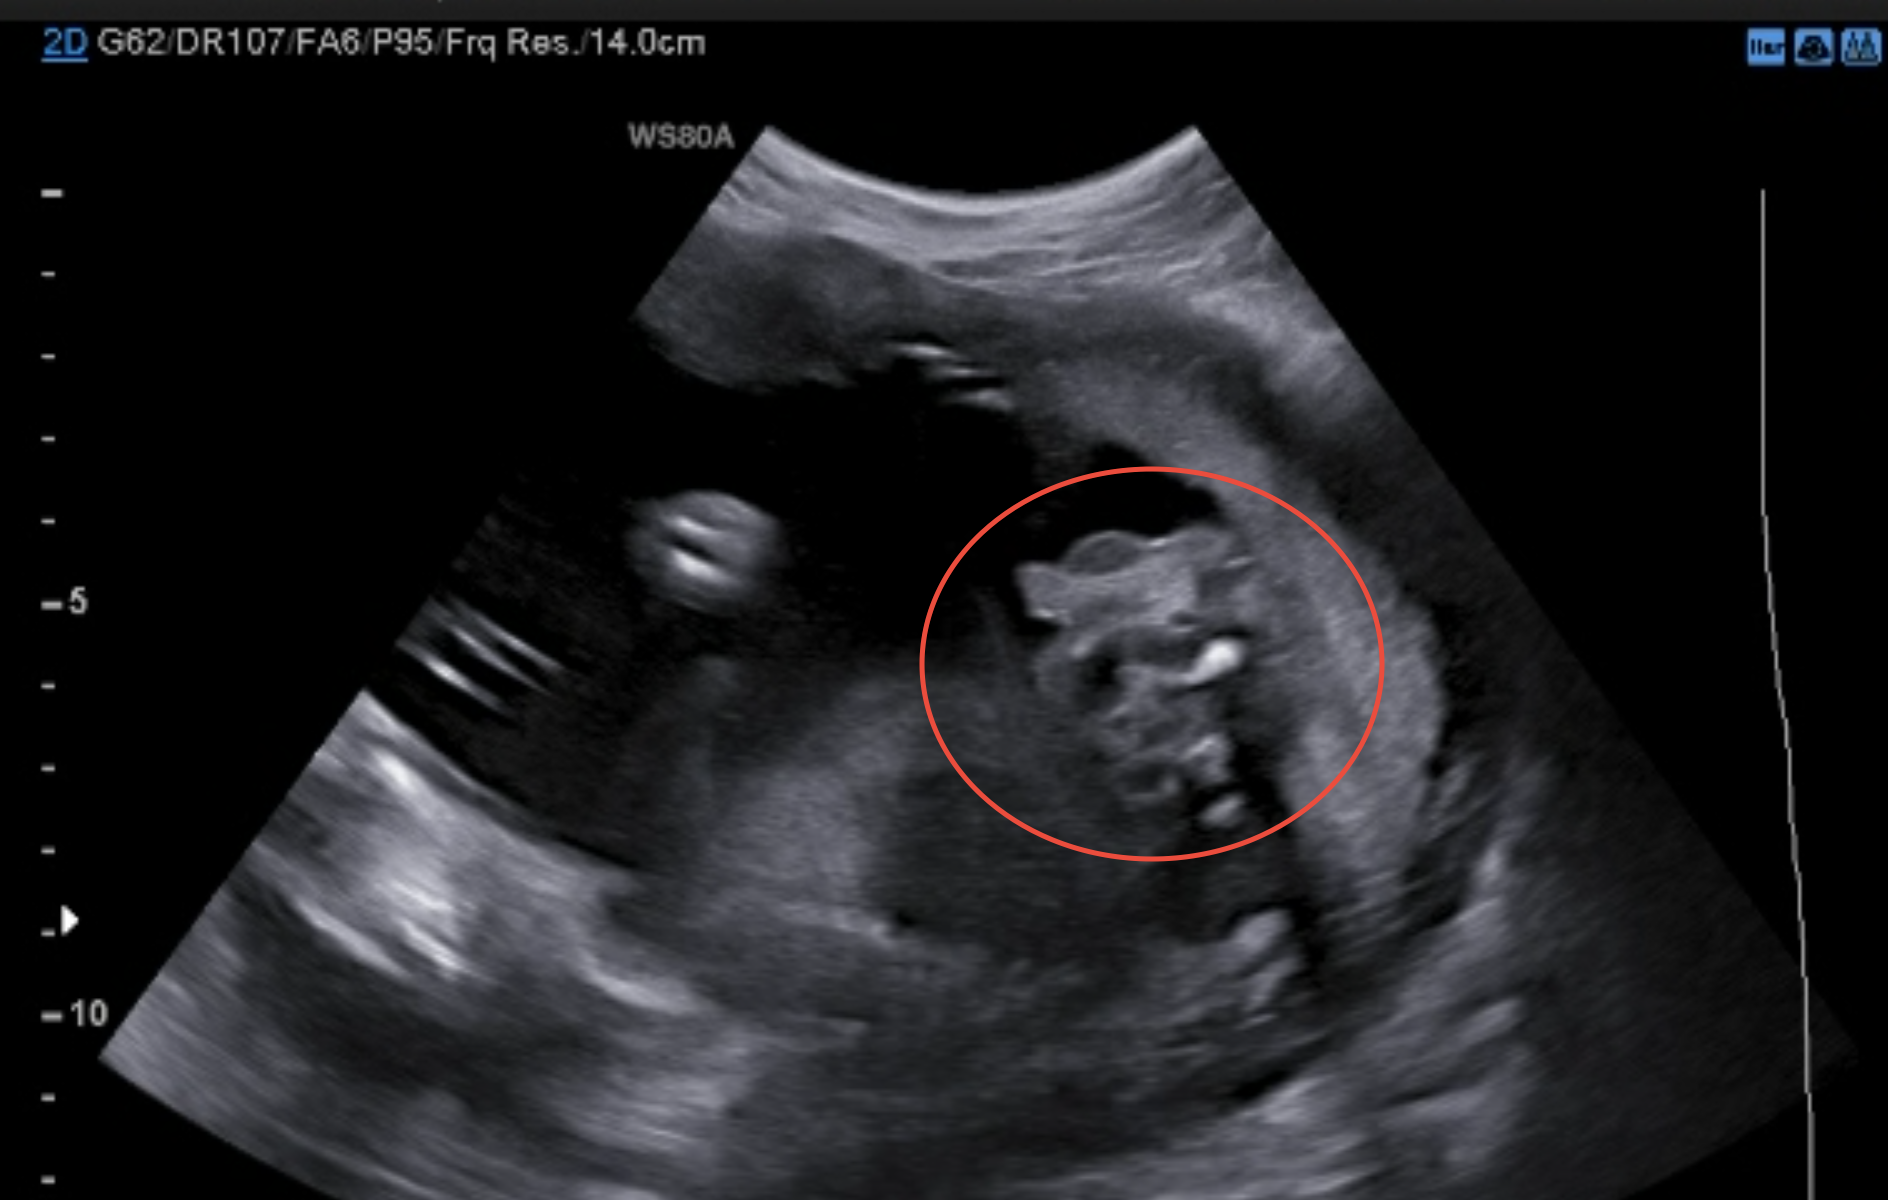

Moc hezky zdravím, chtěla bych se zeptat těch z vás, kdo se vyznáte v ultrazvucích, co přesně je vidět na našem obrázku.. Paní doktorka řekla a ukázala, že "tady to je jasně vidět" a řekla nám pohlaví (nebudu napovídat ;) ), ale já prostě nevidím nic konkrétního, jen šmouhy :D Mohl byste mi někdo nějak popsat, z jakého to je vlastně úhlu a co přesně tam prozrazuje ono pohlaví? Děkuju moc :)